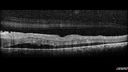

Grade 4 hypertensive retinopathy444 views55 year old man Hhe did have headaches a few weeks ago and also some nausea and vomiting. He noticed for a few weeks the vision in the left eye was blurred and that the vision in the left eye is dark.

VA OD: Dcc20/20

VA OS: Dcc20/100-1

He was admitted directly to ICU for blood pressure control (290 / 170 mmHg)

3 weeks later his VA increased to 20/20 OD, 20/32 OSJan 29, 2019